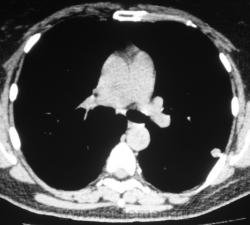

Произведена КТ.

КТ хотелось бы посмотреть в dicom-формате, меняя режимы, но на мой взгляд образование содержит известковые включения. Хотя, я не настаиваю, дождемся мнения коллег.

Нет "волшебных методов", можна поставить диф. ряд. Я бы дала такое заключение: хондрогамартрома, дифференцировать с туберкуломой, периферический рак менее вероятен. Можно жизнь прожить с гамартромой, а может озлиться в саркому. На практике был случай, когда лет 10 наблюдалась классическая скиалогически туберкулома, которая за полгода выросла и оказалась аденокарциномой. Таким образом, при любом раскладе, хирургическое лечение не является ошибкой, но решение об операции на легком должен принимать консилиум.

Дело не в желании, а в смысле. Что тут ещё можно сказать? На мой взгляд-мелкая, частично кальцинированная туберкулома.

Да, более туберкулёма.